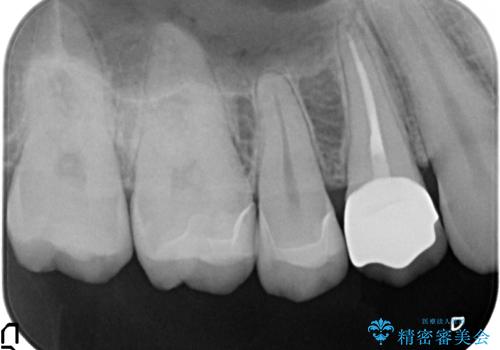

- 27万円(セラミックインレー×2 仮歯・ファイバーコア・ジルコニアクラウン)費用は治療当時の料金となります

虫歯治療は小さい場合にはセラミックインレー、大きな場合や痛みが生じている場合は根管治療ののちクラウンによる機能回復が必要となることが多いです。